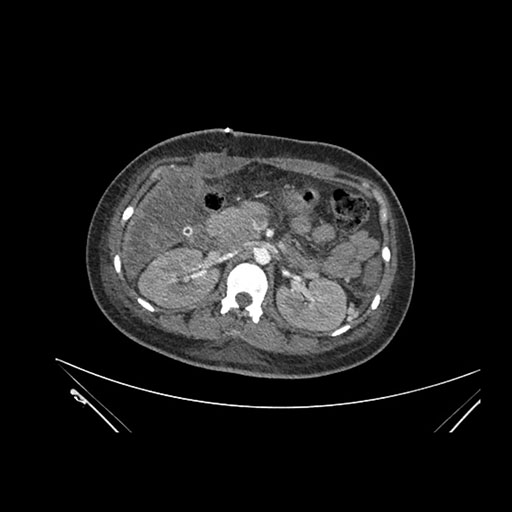

Imaging Analysis

Look through the patient's CT scan to identify any areas of concern for the necessary procedure.

Coronal Arterial

Based on initial findings, which issue(s) would you be most concerned about?